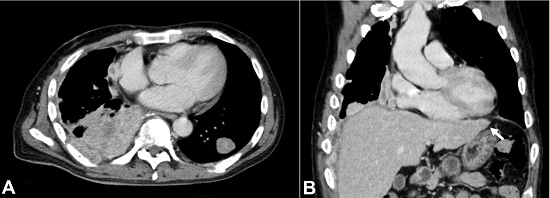

Three cycles of S-1 chemotherapy (tegafur, 5-chloro-2,4-dihydroxypyridine, and potassium oxonate) were administered, with tumor size reduction. Adjuvant radiotherapy and narcotic analgesia were combined afterward. The CT scan performed after six months of the diagnosis revealed an increasing size of the tumors in both lungs (Figure 3A). In addition, two liver nodules were detected (Figure 3B). The growing tumors in the right lung caused obstructive pneumonia, and the patient died of hypoxia six months after the initial presentation.